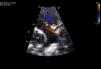

Latente do sexo feminino, com oito meses de idade, com história de má progressão ponderal a partir dos quatro meses e duas pneumonias, aos cinco e oito meses. Ao exame objetivo apresentava polipneia, S3 e sopro holossistólico grau III/VI no ápex com irradiação para a axila. Na radiografia de tórax observou‐se cardiomegalia, com índice cardiotorácico de 60%. O eletrocardiograma mostrou ondas Q>3mm em DI, aVL e V7 e inversão da onda T de V5‐V7, padrão sugestivo de enfarte do miocárdio. O ecocardiograma transtorácico revelou dilatação e disfunção global do ventrículo esquerdo (VE), com diâmetro diastólico (VEdd) 46mm (Z‐Score+12,44), fração de encurtamento (FEnc) 16% e fração de ejeção (FEj) biplano 25,4%, com regurgitação mitral grave por má coaptação dos folhetos. A artéria coronária esquerda (CE) tinha origem no tronco da artéria pulmonar (ALCAPA) (Figuras 1 e 2). Foi referenciada para cirurgia com base exclusivamente na informação destes exames. A correção cirúrgica consistiu na reimplantação da CE na aorta (Figuras 3 e 4). A cirurgia e o pós‐operatório decorreram sem complicações. Teve alta oito dias depois, apresentando redução das dimensões do VE e melhoria significativa da função sistólica global (VEdd 33mm, Z‐Score+5,22, FEnc 23% e FEj biplano 41,3%). Aos três meses após cirurgia a criança está clinicamente bem e com normalização da função ventricular.